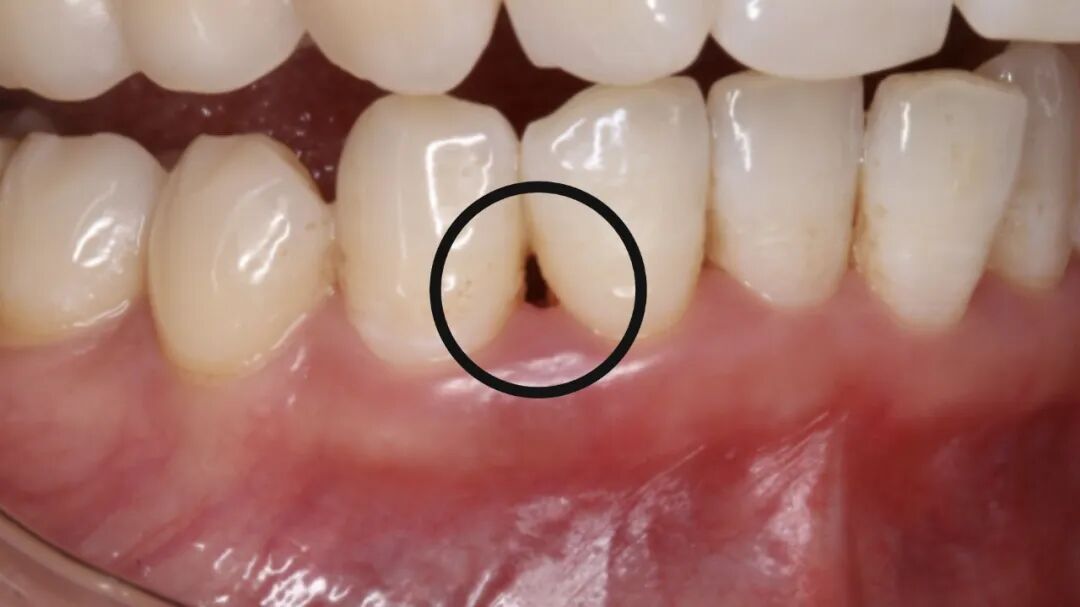

牙石和牙菌斑:隐藏的填充物

长期的牙菌斑和牙石积累不仅是牙周病的罪魁祸首,还在一定程度上“填充”了你的牙缝。当这些牙石被清理掉后,原本被牙石填充的空间就会显露出来,这就让你觉得牙缝变大了。

治疗前

治疗后

牙结石